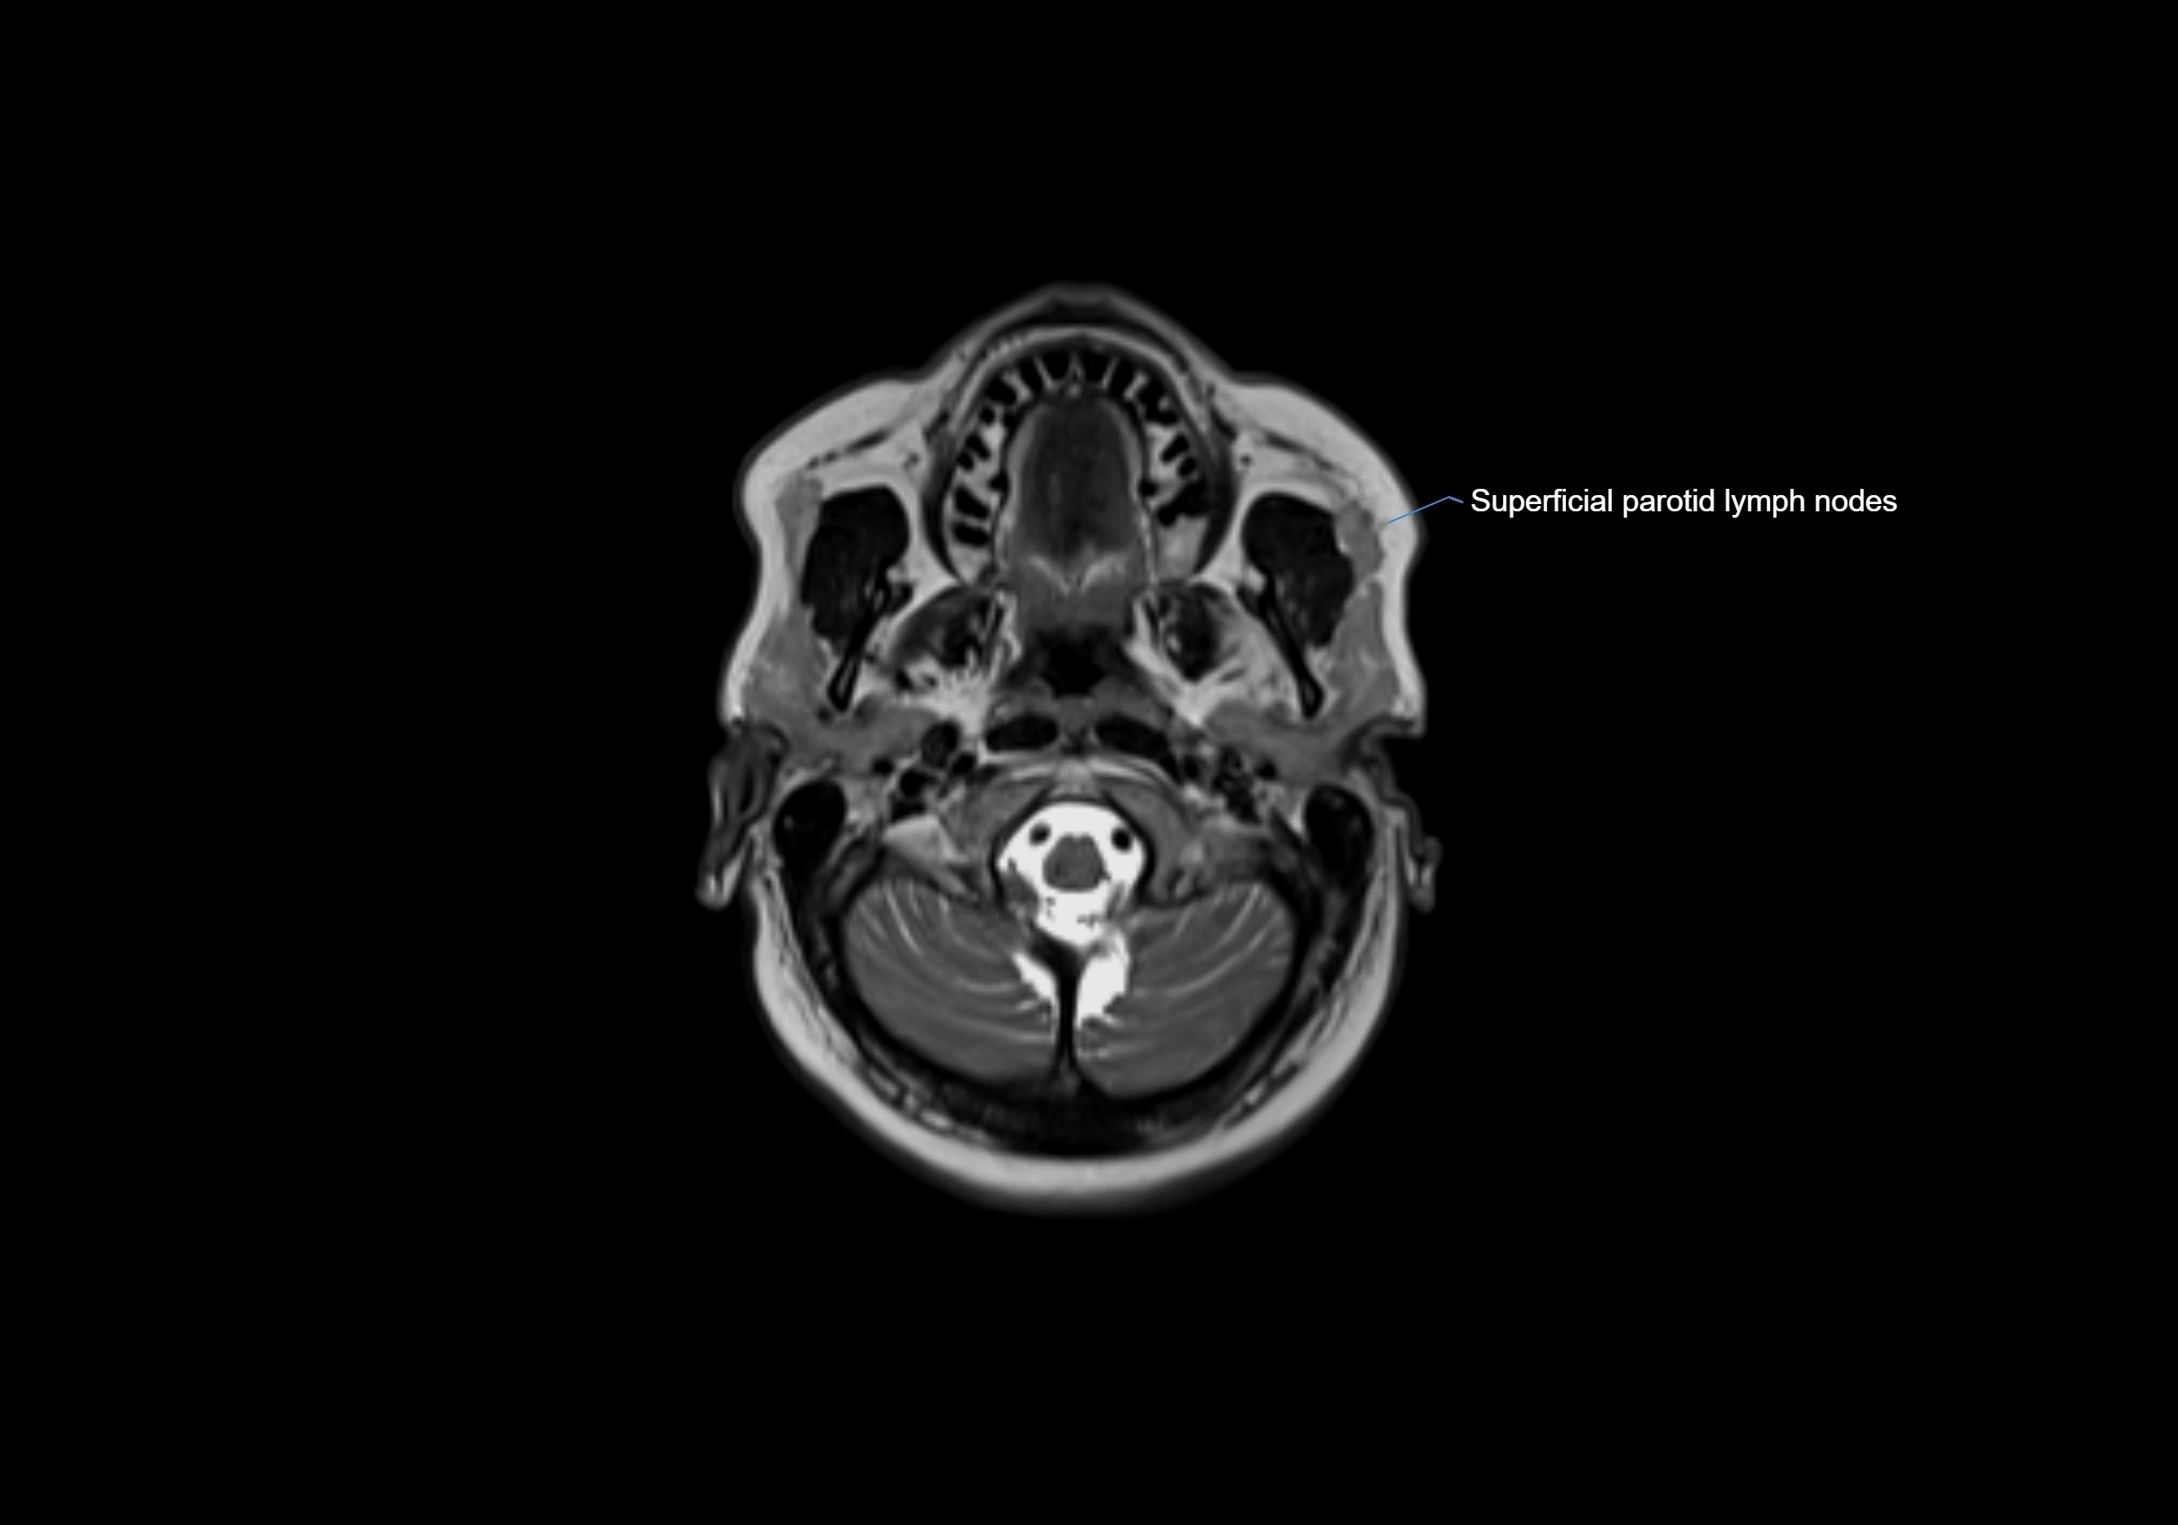

Accessory lymph nodes

Accessory lymph nodes are small, secondary lymph nodes located along the main facial and cervical lymphatic chains, often adjacent to primary lymph nodes, such as preauricular, submandibular, or occipital nodes. They are typically less than 5 mm in diameter, embedded within subcutaneous fat or connective tissue, and may be variable in number and location. These nodes provide additional filtration and immune surveillance for lymph collected from the face, scalp, and neck regions. Accessory lymph nodes are usually non-palpable in healthy individuals but may enlarge in response to infection, inflammation, or metastasis, making them clinically significant.

Location

• Found along primary lymph node chains, including preauricular, submandibular, parotid, and occipital regions

• Embedded in subcutaneous fat or superficial fascia, often lateral or posterior to primary nodes

• Variable in number; may occur unilaterally or bilaterally, depending on individual anatomy

MRI Appearance

T1-weighted images:

• Normal accessory nodes appear as small, oval hypointense to intermediate signal structures within subcutaneous fat

• Surrounded by hyperintense fat, enhancing contrast for visualization

• Pathological nodes may appear enlarged or rounded, sometimes with cortical thickening

T2-weighted images:

• Nodes show intermediate signal, with surrounding fat bright

• Useful for detecting edema, inflammation, or infiltration

• Fatty hilum may appear slightly hyperintense relative to cortex